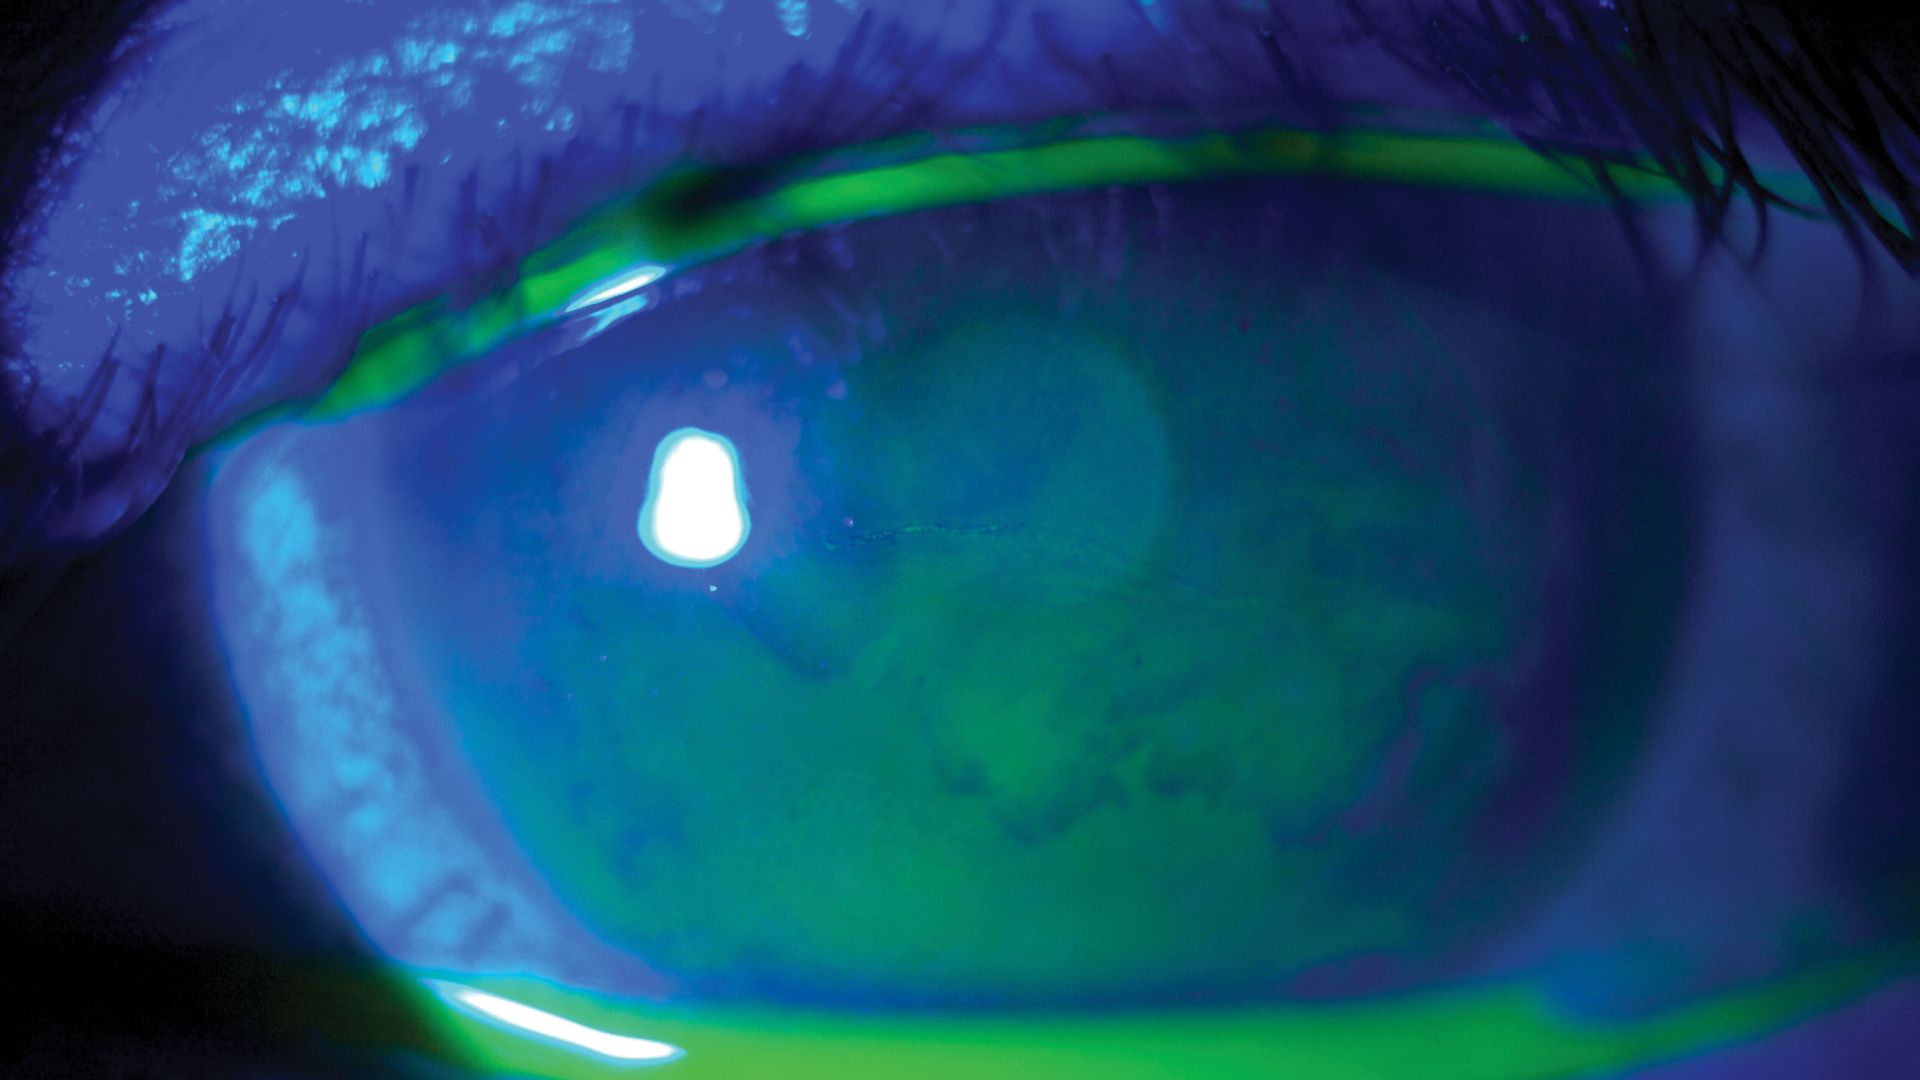

Korneal Topografi